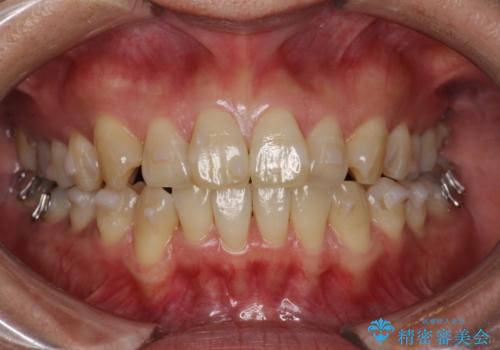

インビザラインによる矯正治療(非抜歯) 前歯の突出と上下の歯並びのガタつきの改善

- 上下の歯並びにガタつきがあり、また、上下前歯の前後のズレが大きく上の前歯が突出しています。

インビザラインではガタつき(叢生)の改善だけでなく、上下の前後的なズレについてもアプローチが可能です。

インビザラインの特色を生かした歯牙移動計画を作成し、非抜歯にて治療を行いました。